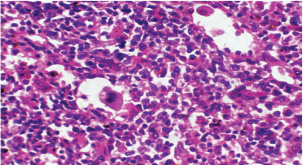

Histopathological examination of rabbits infected with T. annulata (G2) demonstrated progressive pathological alterations in various organs, in contrast to the control group (G1), which exhibited no abnormalities. At 14 days of post-infection, the lungs exhibited moderate alveolar thickening, hyperemia, and the presence of developed schizonts, indicating early tissue involvement (Fig. 4). The liver showed multiple necrotic areas, extensive venous congestion, and parasitized red blood cells, suggesting severe hepatic distress (Fig. 5). The spleen exhibited scattered macrophages containing microschizonts and hemosiderin-laden macrophages, reflecting both immune activation and erythrocyte breakdown (Fig. 6). The kidneys were affected by tubular infiltration with parasitized mononuclear cells (MNCs) (Fig. 7), whereas the mesenteric lymph nodes showed marked architectural disruption and merozoite aggregation (Fig. 8), suggesting significant immune system involvement.

At 21 days post-infection, the lungs display moderate venous dilation and congestion, with abnormal leukocytes, indicating ongoing vascular compromise (Fig. 9). The liver showed necrotic changes in the fibrous capsule region, focal inflammatory cell infiltration, and intact hepatic cords, indicating sustained but localized damage (Fig. 10). The spleen exhibited plasma cell and macrophage proliferation within the red pulp, mild sinus dilation, and a few megakaryocytes, suggesting chronic immune activation (Fig. 11). The kidneys showed atrophic glomerular tufts and cystic dilation of adjacent tubules, indicating worsening renal pathology (Fig. 12). The mesenteric lymph nodes showed lymphoid follicles containing abnormal plasma cells and macrophages within the necrotic foci (Fig. 13).

Fig. 6. A histopathological section of the spleen of (G2) at 14 days postinfection shows the scattered presence of macrophages containing micro-schizont (black arrow) and hemosiderin laden macrophages (red arrow) (H&E stain X 40).

Fig. 8. A histopathological section of mesenteric lymph node of (G2) at 14 days postinfection showing marked disruption of the lymph node architecture (red arrow) with evidence of merozoites aggregation (black arrow) (H&E stain X 40).